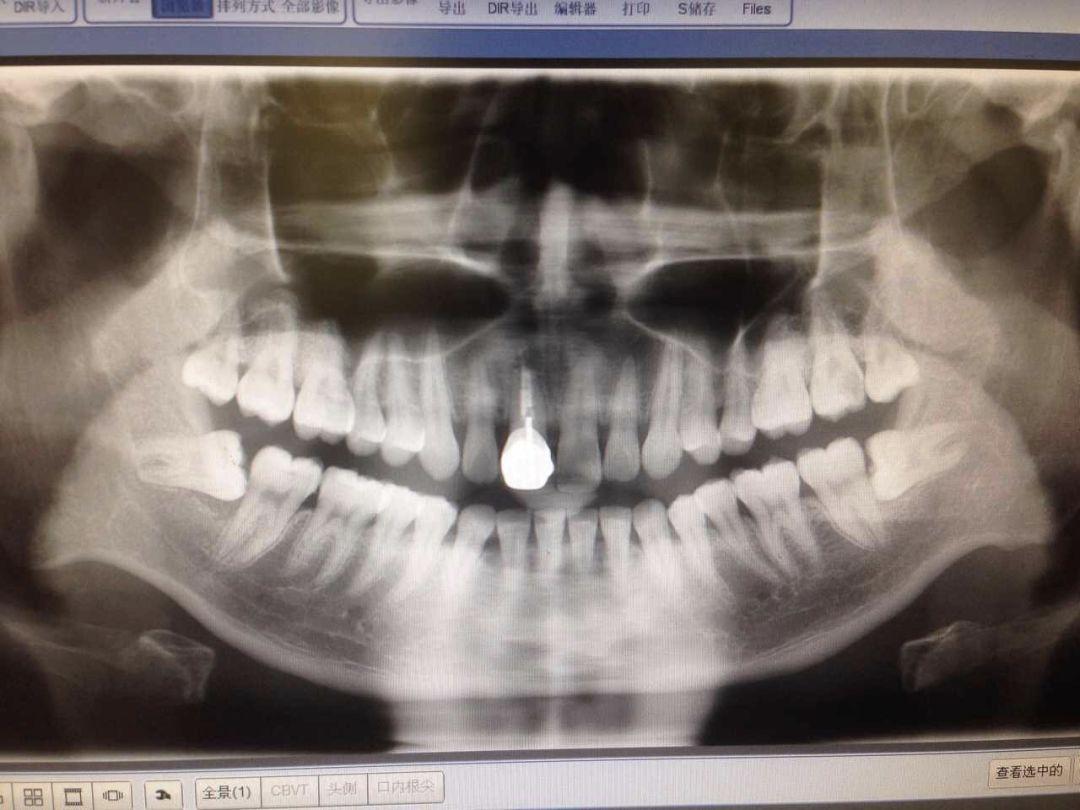

智齒有不同的長法,我們今天按照 easy - normal - hard - hell 這 4 種難度等級來介紹…在拔智齒之前,一般要簽署一個手術知情書。拔智齒和普通拔牙不一樣,這都已經算是外科手術對待了。首先是拍個 2 維的 X 片或是更精細的三維的 CT,確定智齒的位置和模樣,牙醫(yī)才能確定拔除方案(和價格)...

來帶領大家一起重溫下小編這張牙片,兩顆下智齒都是躺在牙床里的,有一點點頭露出來,和旁邊的牙齒就形成一個不容易刷到的面。